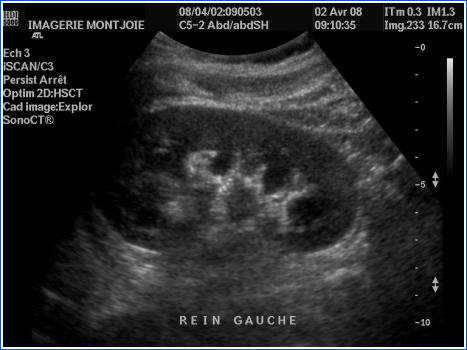

Bilan d’une insuffisance rénale chez un patient: comment est le rein?

Normal

petit, avec dédifférenciation cortico-médullaire => en faveur d’une maladie rénale chronique